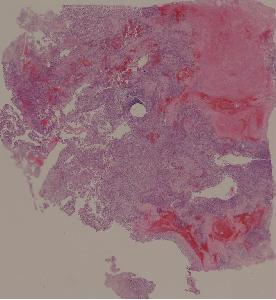

34. Osteosarcoma

低倍视野